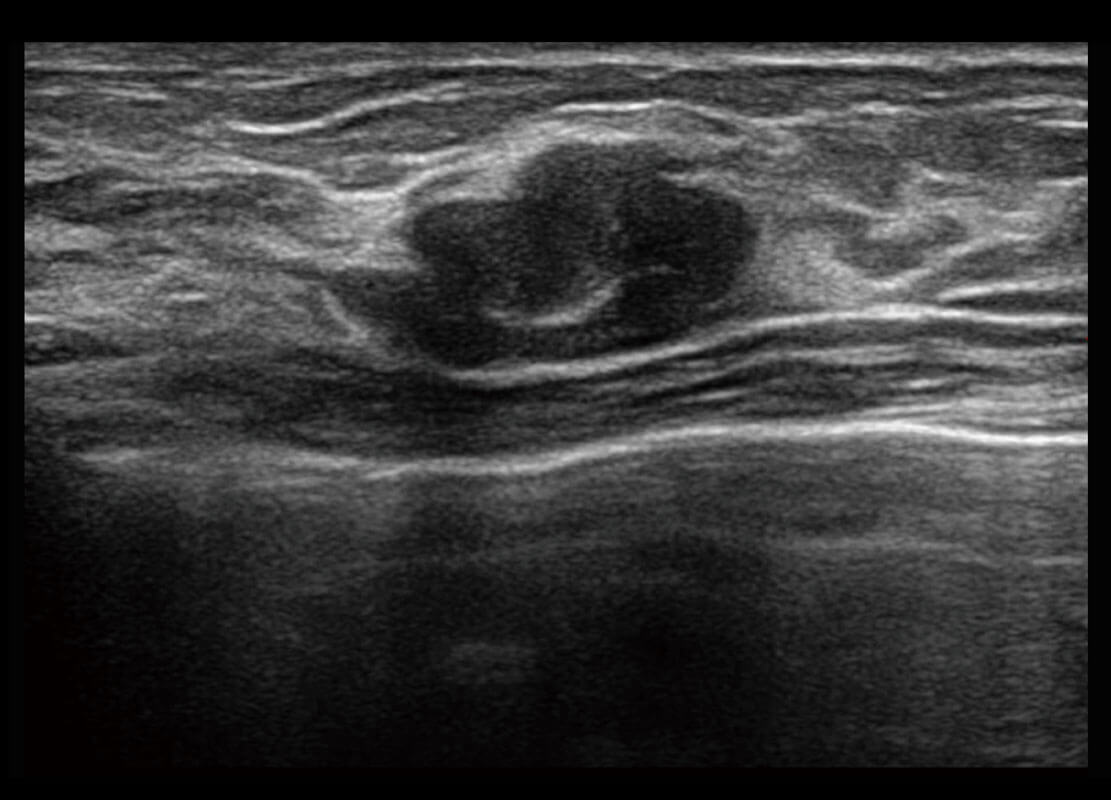

P60搭载宽频带线阵探头、宽景成像、弹性成像技术,为您提供乳腺应用方案。P60支持高频相控阵探头、线阵探头、腹部高频探头、腹部微凸探头等,丰富的探头群搭载敏感的彩色血流成像,适用于新生儿多种脏器检测要求,满足新生儿筛查需求。

乳腺导管癌